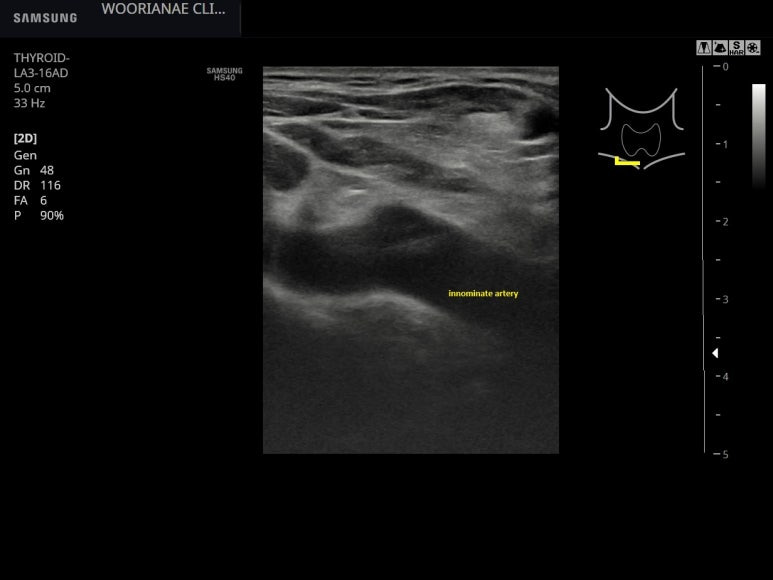

상기 모습이 림프절에 가깝지 않으나 주변부 다른 림프절이 비대칭적으로 커져있나 찾아보는데 특별해 보이지 않으며.. 경동맥 아래 무명동맥까지 관찰